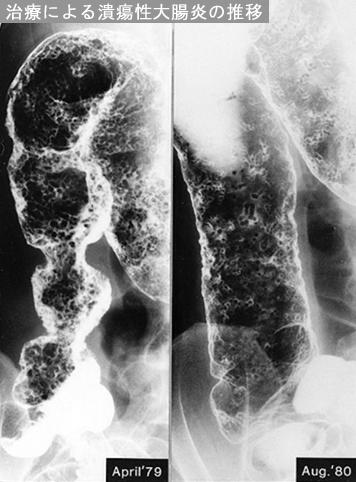

Posted by: Tokyo Pref., 国立癌中心中央病院和九州癌中心共同完成

[ Image ID:12232 ]